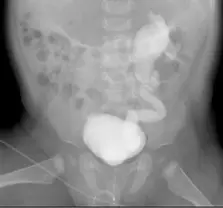

- 檢查方法判斷:影像為一張小兒骨盆與腹部的前後向(AP)X 光片(由未完全癒合的骨盆與股骨頭骨骺線可判斷為孩童)。影像中可觀察到膀胱充滿極高密度的顯影劑,且顯影劑異常地由下而上逆流至單側的輸尿管與腎盂。這種藉由尿道插管逆行性注入顯影劑,使膀胱達到極高對比度的表現,是「排尿道膀胱尿道攝影術(VCUG)」的典型特徵。若為靜脈注射的 IVU,顯影劑會由雙側腎臟順行性排泄而下,初期膀胱內的顯影劑濃度不會如此飽滿且單純呈現單側逆流。

- 病灶位置判讀:依據標準放射線影像常規,影像的右側代表病患的「左側」(Left),影像的左側代表病患的「右側」(Right)。

- 病理發現:在影像的右側(即病患左側)可見顯影劑逆流,該側輸尿管出現極度嚴重的擴張(dilatation)與扭曲(tortuosity),腎盂與腎盞也明顯擴張且形狀變鈍。此影像特徵屬於典型的高分級「膀胱輸尿管逆流(Vesicoureteral reflux, VUR)」,大約為 Grade IV 或 Grade V。

- (C) voiding cystourethrography (VCUG)、left:影像顯示逆行性充填的 VCUG 檢查,且病患的「左側」(影像右側)集尿系統出現明顯的擴張、扭曲與逆流現象,完全符合影像所見。為正確選項。

正確答案為 C。 由影像中膀胱充滿高密度顯影劑並出現由下往上的單側逆流,可明確判斷此為經導管逆行性注入顯影劑的排尿道膀胱尿道攝影術(VCUG),而非靜脈注射的 IVU。依據醫學影像左右相對的判讀原則(影像的右側為病患的左側),可確認出現嚴重擴張與扭曲的逆流病灶位於病患的左側(left)集尿系統。